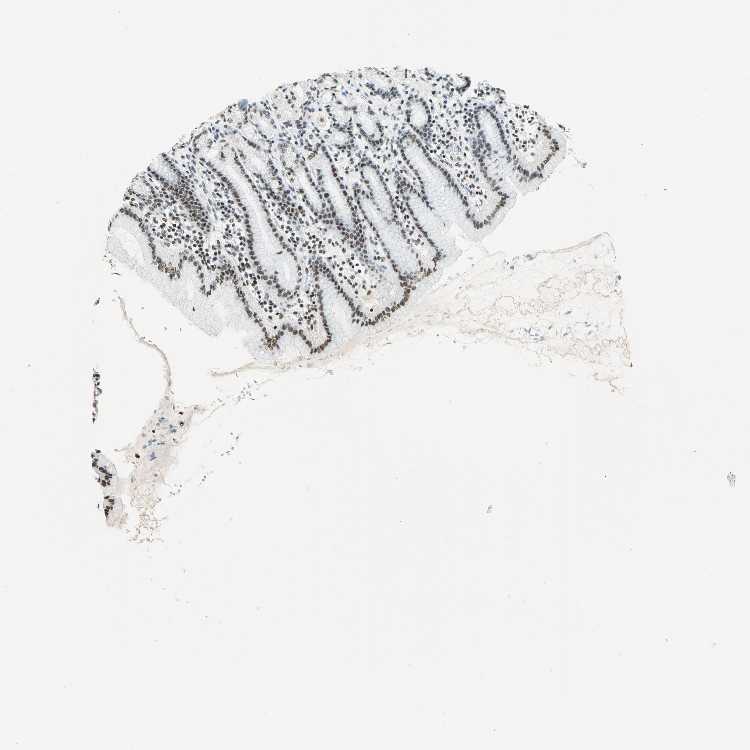

STOMACH 1 - Antibody stainingi

Antibody staining in the annotated cell types in the current human tissue is reported as not detected, low, medium, or high, based on conventional immunohistochemistry profiling in selected tissues. This score is based on the combination of the staining intensity and fraction of stained cells.

Each image is clickable and will lead to virtual microscopy that enables deeper exploration of all samples and also displays staining intensity scores, fraction scores and subcellular localization as well as patient and tissue information for each sample.

Antibody HPA006385Antibody CAB004611

Glandular cells MediumMedium

STOMACH 2 - Antibody stainingi

Glandular cells HighHigh